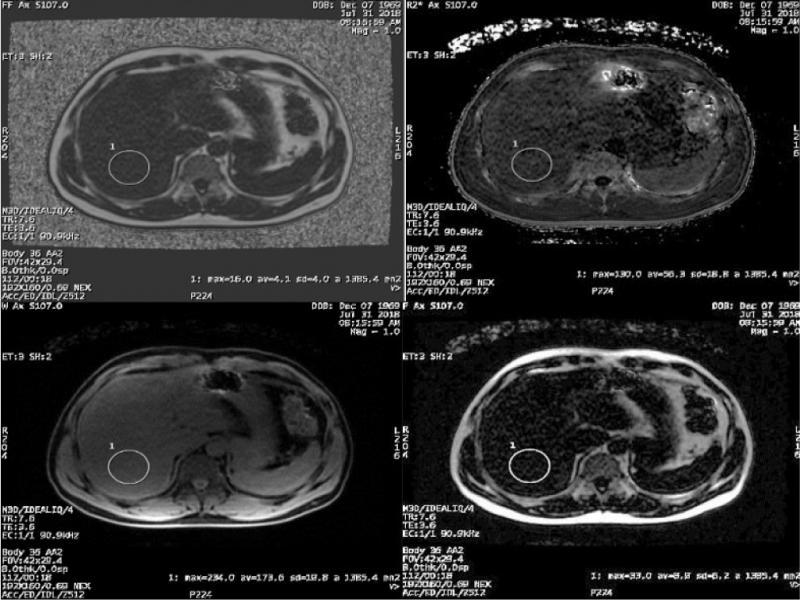

Fig. 2.